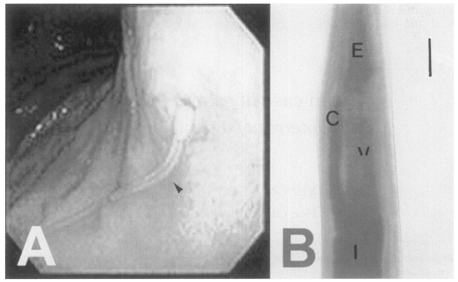

The patient, residing in Chungju-shi, Chungchungbuk-do, was a 34-year-old man. He was admitted to the Department of Internal Medicine in Konkuk University Hospital on Dec 13, 1994. The chief complaint of the patient was prickling epigastric pain and nausea, which developed two days after eating raw marine fish at Chonan-shi, Chungchungnam-do. He was diagnosed as having gastroenteritis. On physical examination, rebound tenderness was positive at the epigastrium, and no specific abnormal findings were revealed from laboratory examinations. Gastrofiberscopic exmaination was performed under the impression of anisakiasis. A long white, yellowish nematode larva invading the gastric mucosa was found in the fundus region and removed (

Fig. 1A).

The recovered worm was fixed in 10% formalin, cleared in alcohol glycerine and mounted in glycerin jelly. The mounted specimen was observed and measured under a light microscope. The nematode larva is slender and the mouth is surrounded by three lips without a boring tooth. The intestinal cecum is stretched anteriorly to the level of one-third portion of the ventriculus (

Fig. 1B). The tail is conical shaped, and reproductive organs are not developed.

The worm measured 34.50 mm long (L) and 0.84 mm wide (W). The total length of the esophagus (E) was 3.38 mm. The ventriculus (V), 1.25 mm long, is directly connected to the muscular esophagus (M), 2.13 mm long, without any appendage. The cecum (C) 1.13 mm, tail 0.12 mm. The morphological indices of the worm are as follows; α(L/W) = 27.60; β1(L/E) = 10.21; β2(L/M) = 15.81; β3(L/V) = 27.60; γ(L/C) = 30.53. From the morphological characteristics and indices, the worm is identified as the 3rd stage larva of P. decipiens.

Fig. 1The larva of Pseudoterranova decipiens found in the stomach of 34-year old patient. A, Gastrofundoscopic view of the present case showing a long white-yellowish larva penetrating the gastric mucosa in the fundus (arrowhead). B, Ventricular level of the worm showing the esophagus (E), ventriculus (V), intestine (I) and intestinal cecum (C). Bar = 300 µm.